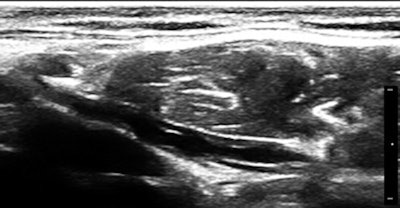

About the same time that we saw the first case, an adult male patient was referred for a vague reason that seemed to have something to do with morbid obesity and failure to lose weight, except through the use of diuretics. He had been hospitalized a few months earlier with pneumonia. The patient was very pleasant but quite enormous, and I really worried that I would not be able to see much with my equipment.

However, as soon as the probe touched the right upper quadrant (I tend to start everything with the liver), it was obvious that there was massive ascites with no increase in abdominal wall or other fat. The fluid was echo-free, and there were no peritoneal studs. The liver and kidneys appeared normal, hepatic veins were patent and normal in caliber, and a brief cardiac survey was normal as well. In a few minutes of scanning, there was a major finding that was a complete surprise and most of its most serious causes were eliminated from consideration. I just love the diagnostic power of ultrasound, especially in a completely exploratory role.

The skin of the lower abdomen is bubbly from lymphedema, and there was a large subcutaneous, paraumbilical sac that opened into the peritoneal cavity.

Remember the lab dogs with surgical ascites? If you had been diligent in your reading about lymphatics, you would have come across the fact that the most common cause of ascites globally is filariasis, afflicting more than 100 million people where mosquitoes are infested with Wuchereria bancrofti and Brugia malayi. The parasites gain entry into superficial lymphatics and propagate centrally, leaving occluded channels in their migratory wake.

So, of course, we had a look at the thoracic duct, which had an abnormal appearance (image below). The technique of visualizing the terminal portion of the thoracic duct, adjacent to the left jugular vein, was published by Seeger et al (Radiology, September 2009, Vol. 252:3, pp. 897-904).

Filariasis usually afflicts legs or genitals, ascending from infections acquired from walking barefoot through an infested area. Our patient happened to be an armorer and professional rifleman who had used a prone firing position when instructing in the tropics, hence the anterior lower abdominal entry of the parasites.